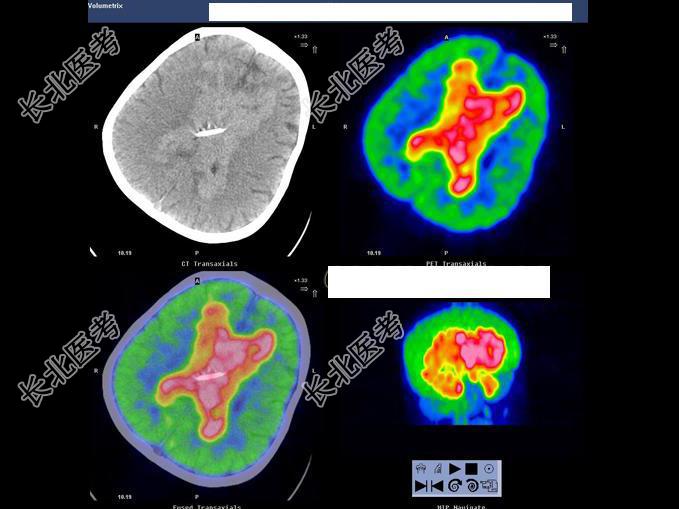

- 多项选择题男,7岁, 2岁时因头痛而就诊,MRI示脑积水、颅内(小脑蚓部及蝶鞍)见多发恶性肿瘤, 临床诊断为髓母细胞瘤。未行手术治疗,多年来一直行放、化疗治疗, 最后一次化疗1个月前结束。因腹胀、恶心、呕吐1周而就诊,CT示: 双侧侧脑室充满肿瘤病灶,PET/CT全身显像如图。正确的表述是 ( )

A、脑干及颈段、胸段、上腰段脊髓内见长条状高代谢病灶,考虑为肿瘤向脑干及大部分脊髓播散、种植转移

B、正常情况下脊髓内无明显放射性浓聚,当出现椎管内肿瘤转移则可表现为18F-FDG明显浓聚,呈“辫子征”

C、肿瘤同时向双侧丘脑及豆状核浸润、侵犯;蝶鞍内块状高代谢病灶,考虑为转移灶

D、肿瘤复发并沿双侧侧脑室弥漫性浸润